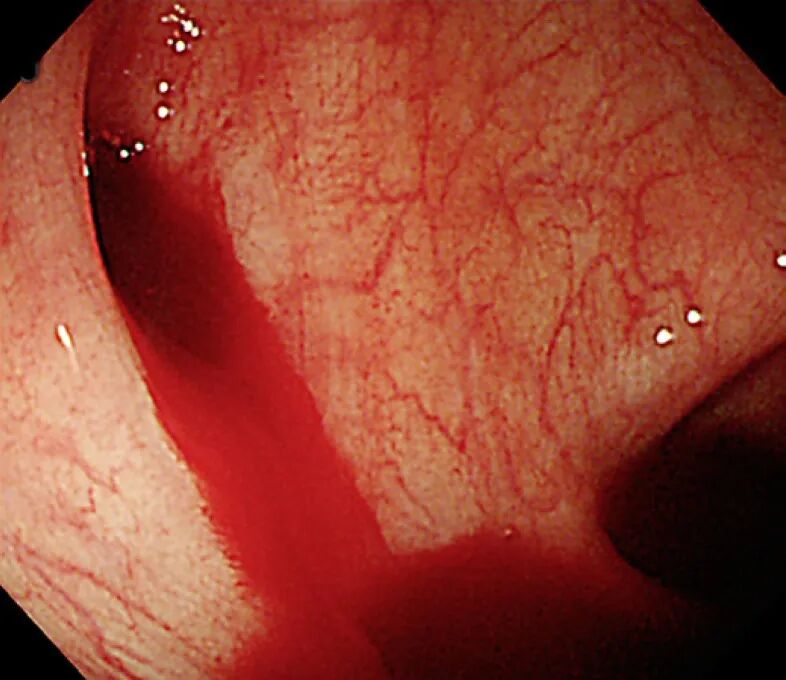

正在出血的肠道憩室病

图片来源:colonoscopy